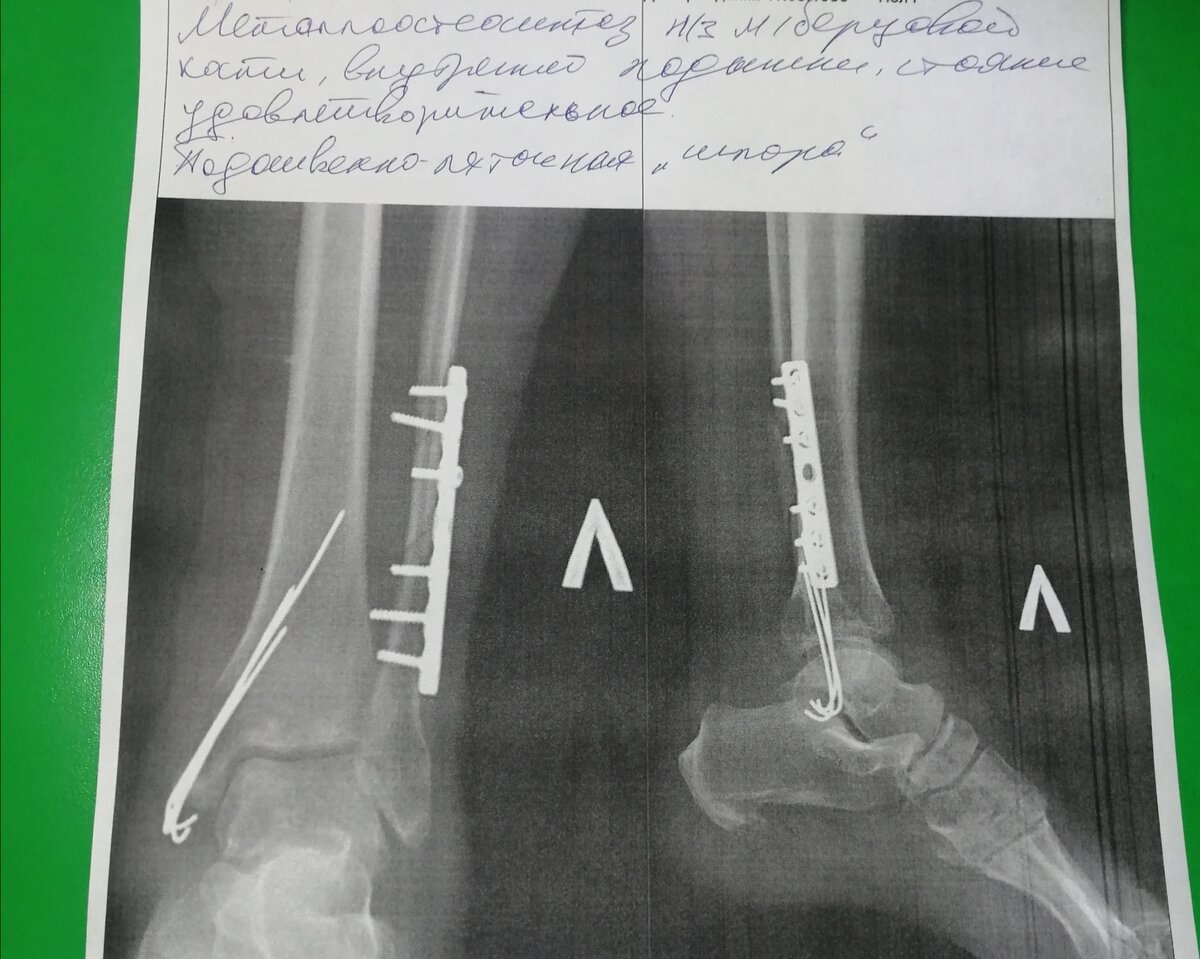

На последнем снимке врач сказал, что видит сращение, но я лично там чего-то выдающегося не увидела. Вот, думаю, сравню сращение, которое было 1,5 месяца назад и сейчас.

Это старый рентген, видно, что кости еще не срослись. Но врач сказал, что идет сращение

После рентгена, на снимке, даже я увидела, что картина маслом!

Однозначно видно, что кость визуально срослась. Даже, я это вижу.

Преисполненная надежд, я зашла к врачу, и он, конечно, подтвердил мои предположения. Говорит, уже и костная мозоль есть, и все хорошо срослось. Теперь дело за малым ( самом большом!), разрабатывать лодыжку.

Свежайший рентгент! Если на лодыжке как будто не так сильно видно, то уж на малой берцовой отлично видно сращение!!!